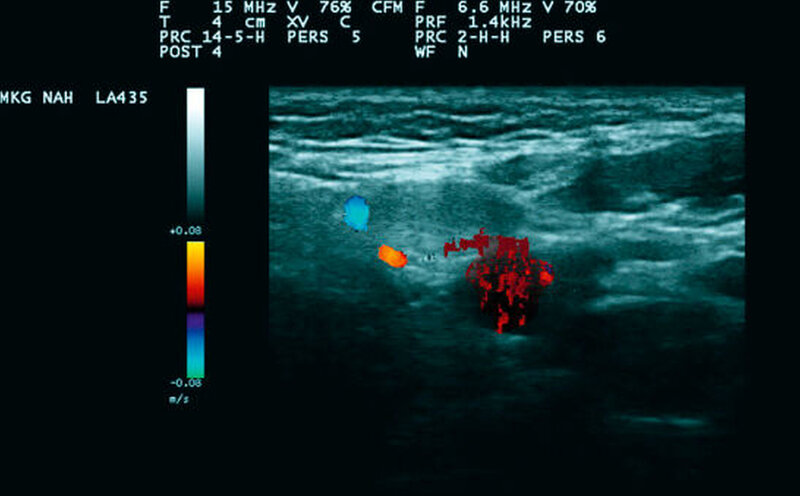

Somit stand differenzialdiagnostisch ein malignes Melanom im Raum. Vor diesem Hintergrund wurde bei sonomorphologisch einzelnen, ipsilateralen, aber zum Teil deutlich vergrößerten Lymphknoten (Abbildungen 2a und 2b) eine Sentinellymphknotenbiopsie durchgeführt, um für den potenziellen Fall des Vorliegens eines malignen Melanoms die Sicherheit für die Patientin zu erhöhen. Der Befund am Ohr selbst wurde zur Wahrung der Ästhetik als kleiner Keil entsprechend des atypischen spitzoiden Naevus entfernt (Abbildung 3).